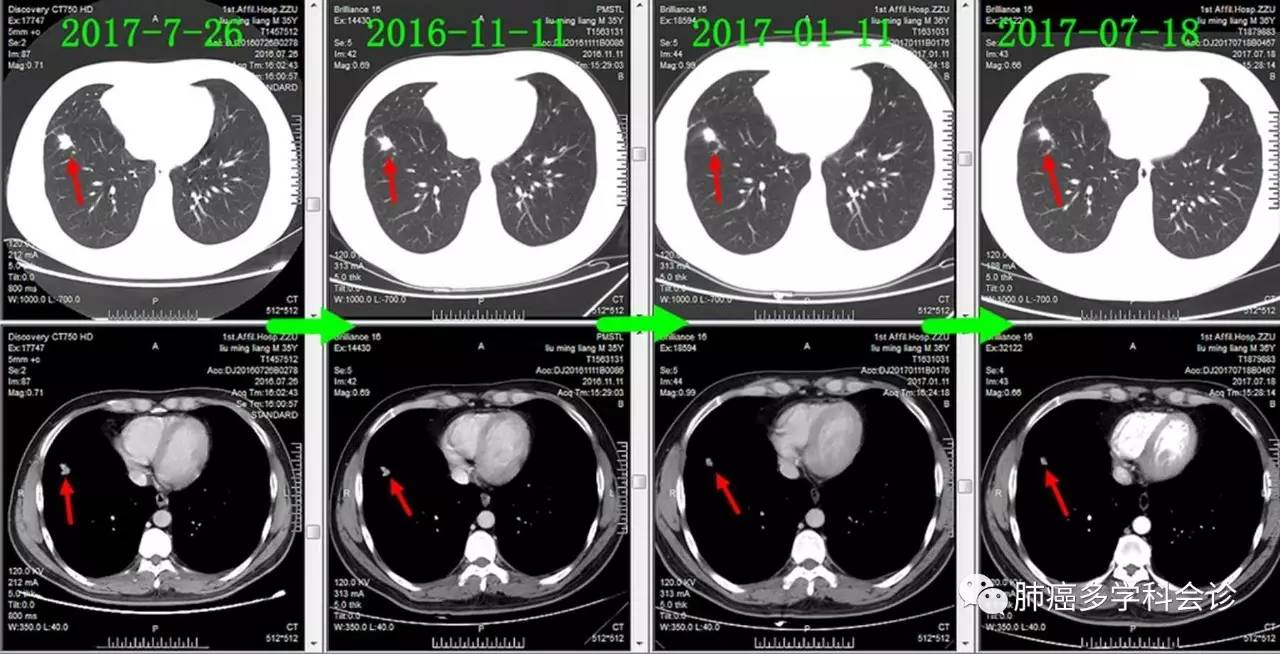

下面通过对比治疗过程中胸部CT变化,展示胸部肿瘤此消彼长的过程:

肺原发灶略有缩小

纵隔肿大淋巴结逐渐缩小

胸膜转移灶消失

食管转移灶从小到大